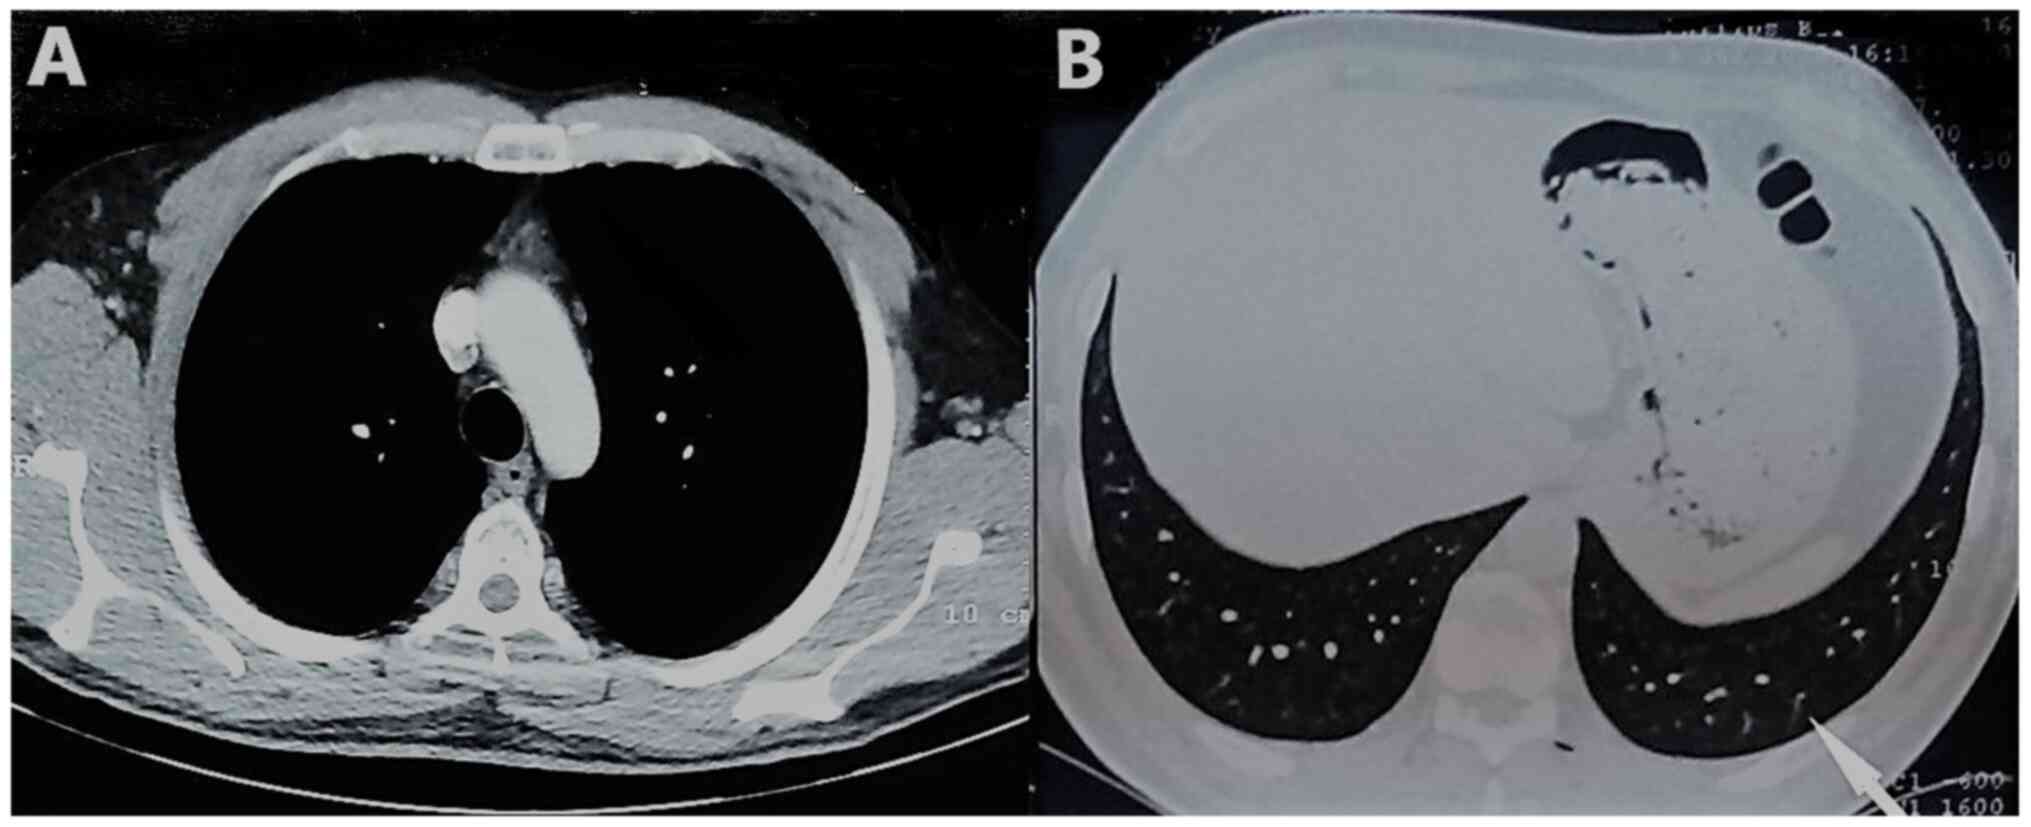

The patient underwent computed tomography (CT) of the chest showing consolidation in the left lower lobe with left pleural effusion, edema of the soft tissue adjacent to the first sternocostal joint and heterogeneity, and invasion of the retrosternal fat (Figs. 2 and 3). In addition, the patient underwent magnetic resonance imaging (MRI) of the chest, to obtain detailed information regarding the pleura and mediastinum, that revealed abnormal soft tissue with dimensions at transverse level 7.0x1.3 cm, containing cystic lesions, adjacent to the first sternocostal joint, indicating inflammation in sternocostal cartilage. MRI also revealed contrast enhancement of the ipsilateral mediastinal pleura, imaging compatible with mediastinitis (Fig. 4).

Figure 2

Chest computed tomography (mediastinal window) shows edema of the soft tissue adjacent to the first sternocostal joint and retrosternal fat heterogeneity/invasion. A, anterior; P, posterior.